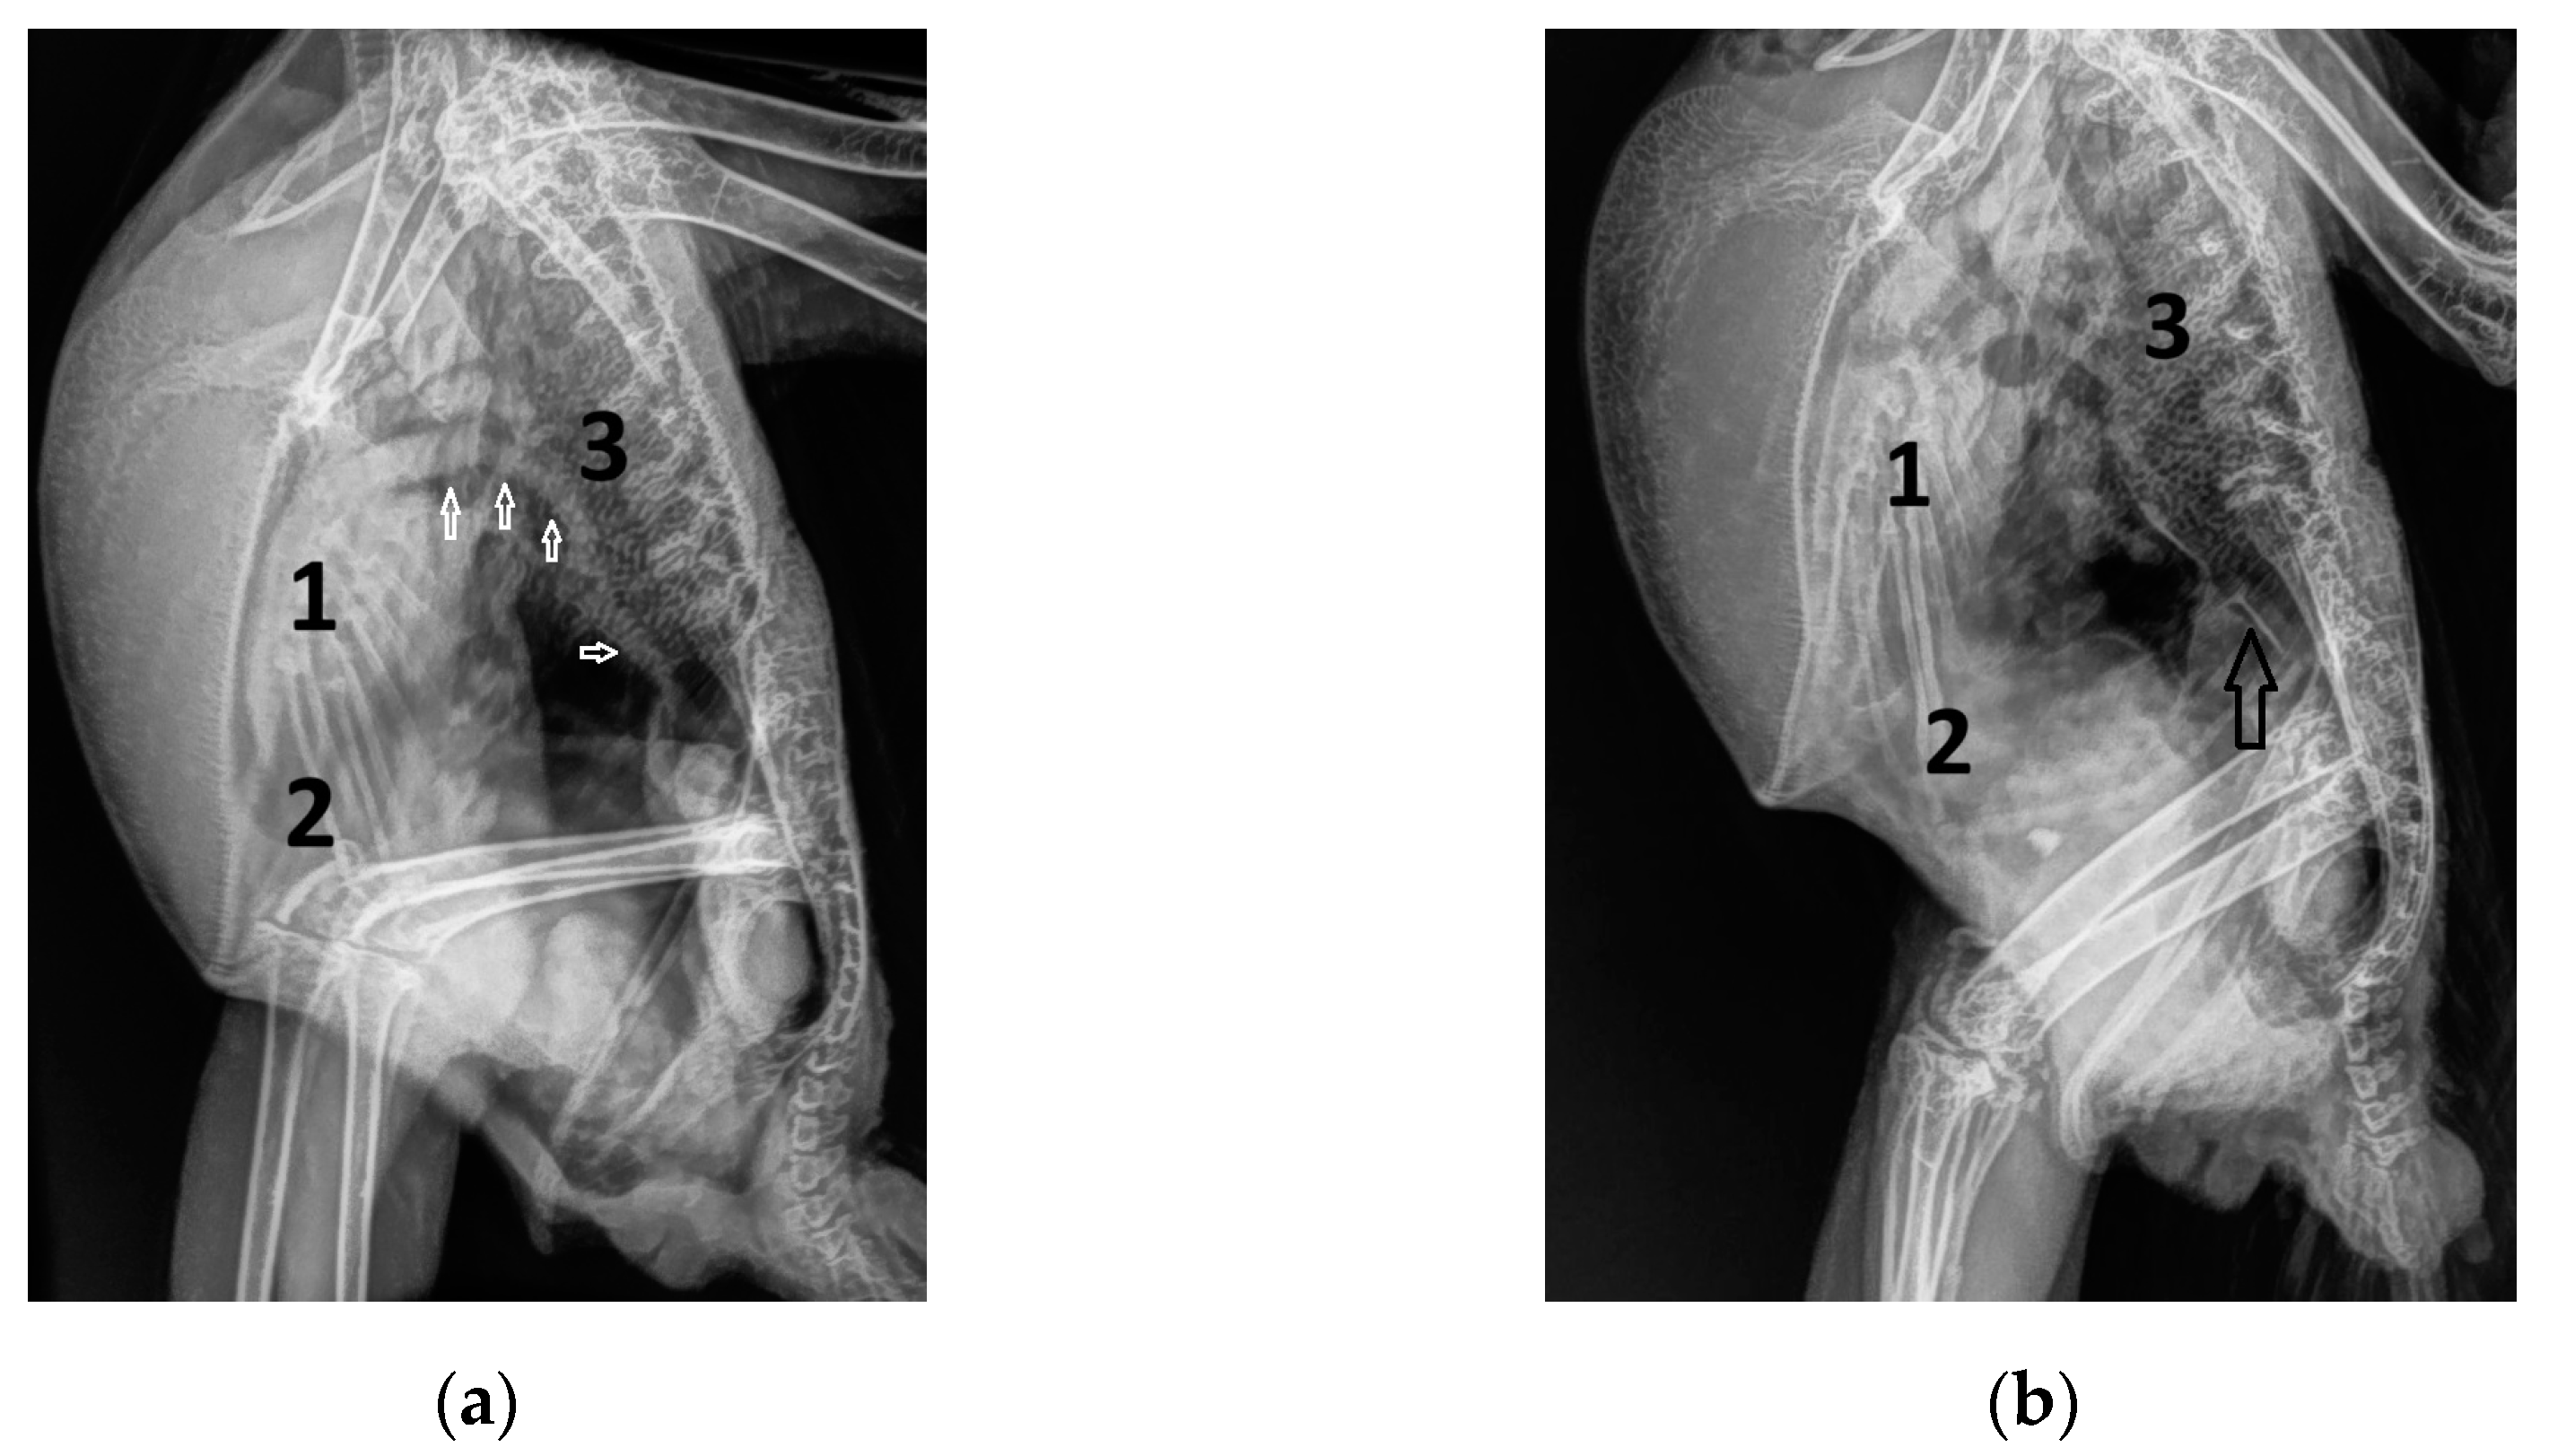

3. Results

3.1. Shape of PAFP and AOFP of Grey Parrots

3.2. The Influence of Heart Failure on the Shape of the PAFP and AOFP

3.3. Influence of the Heart Rate on the Pulmonary and Aortic Blood Flow Profiles of the GPs

3.5. Correlation of the Pulmonary and Aortic Blood Flow Profiles with Different Heart Diameters